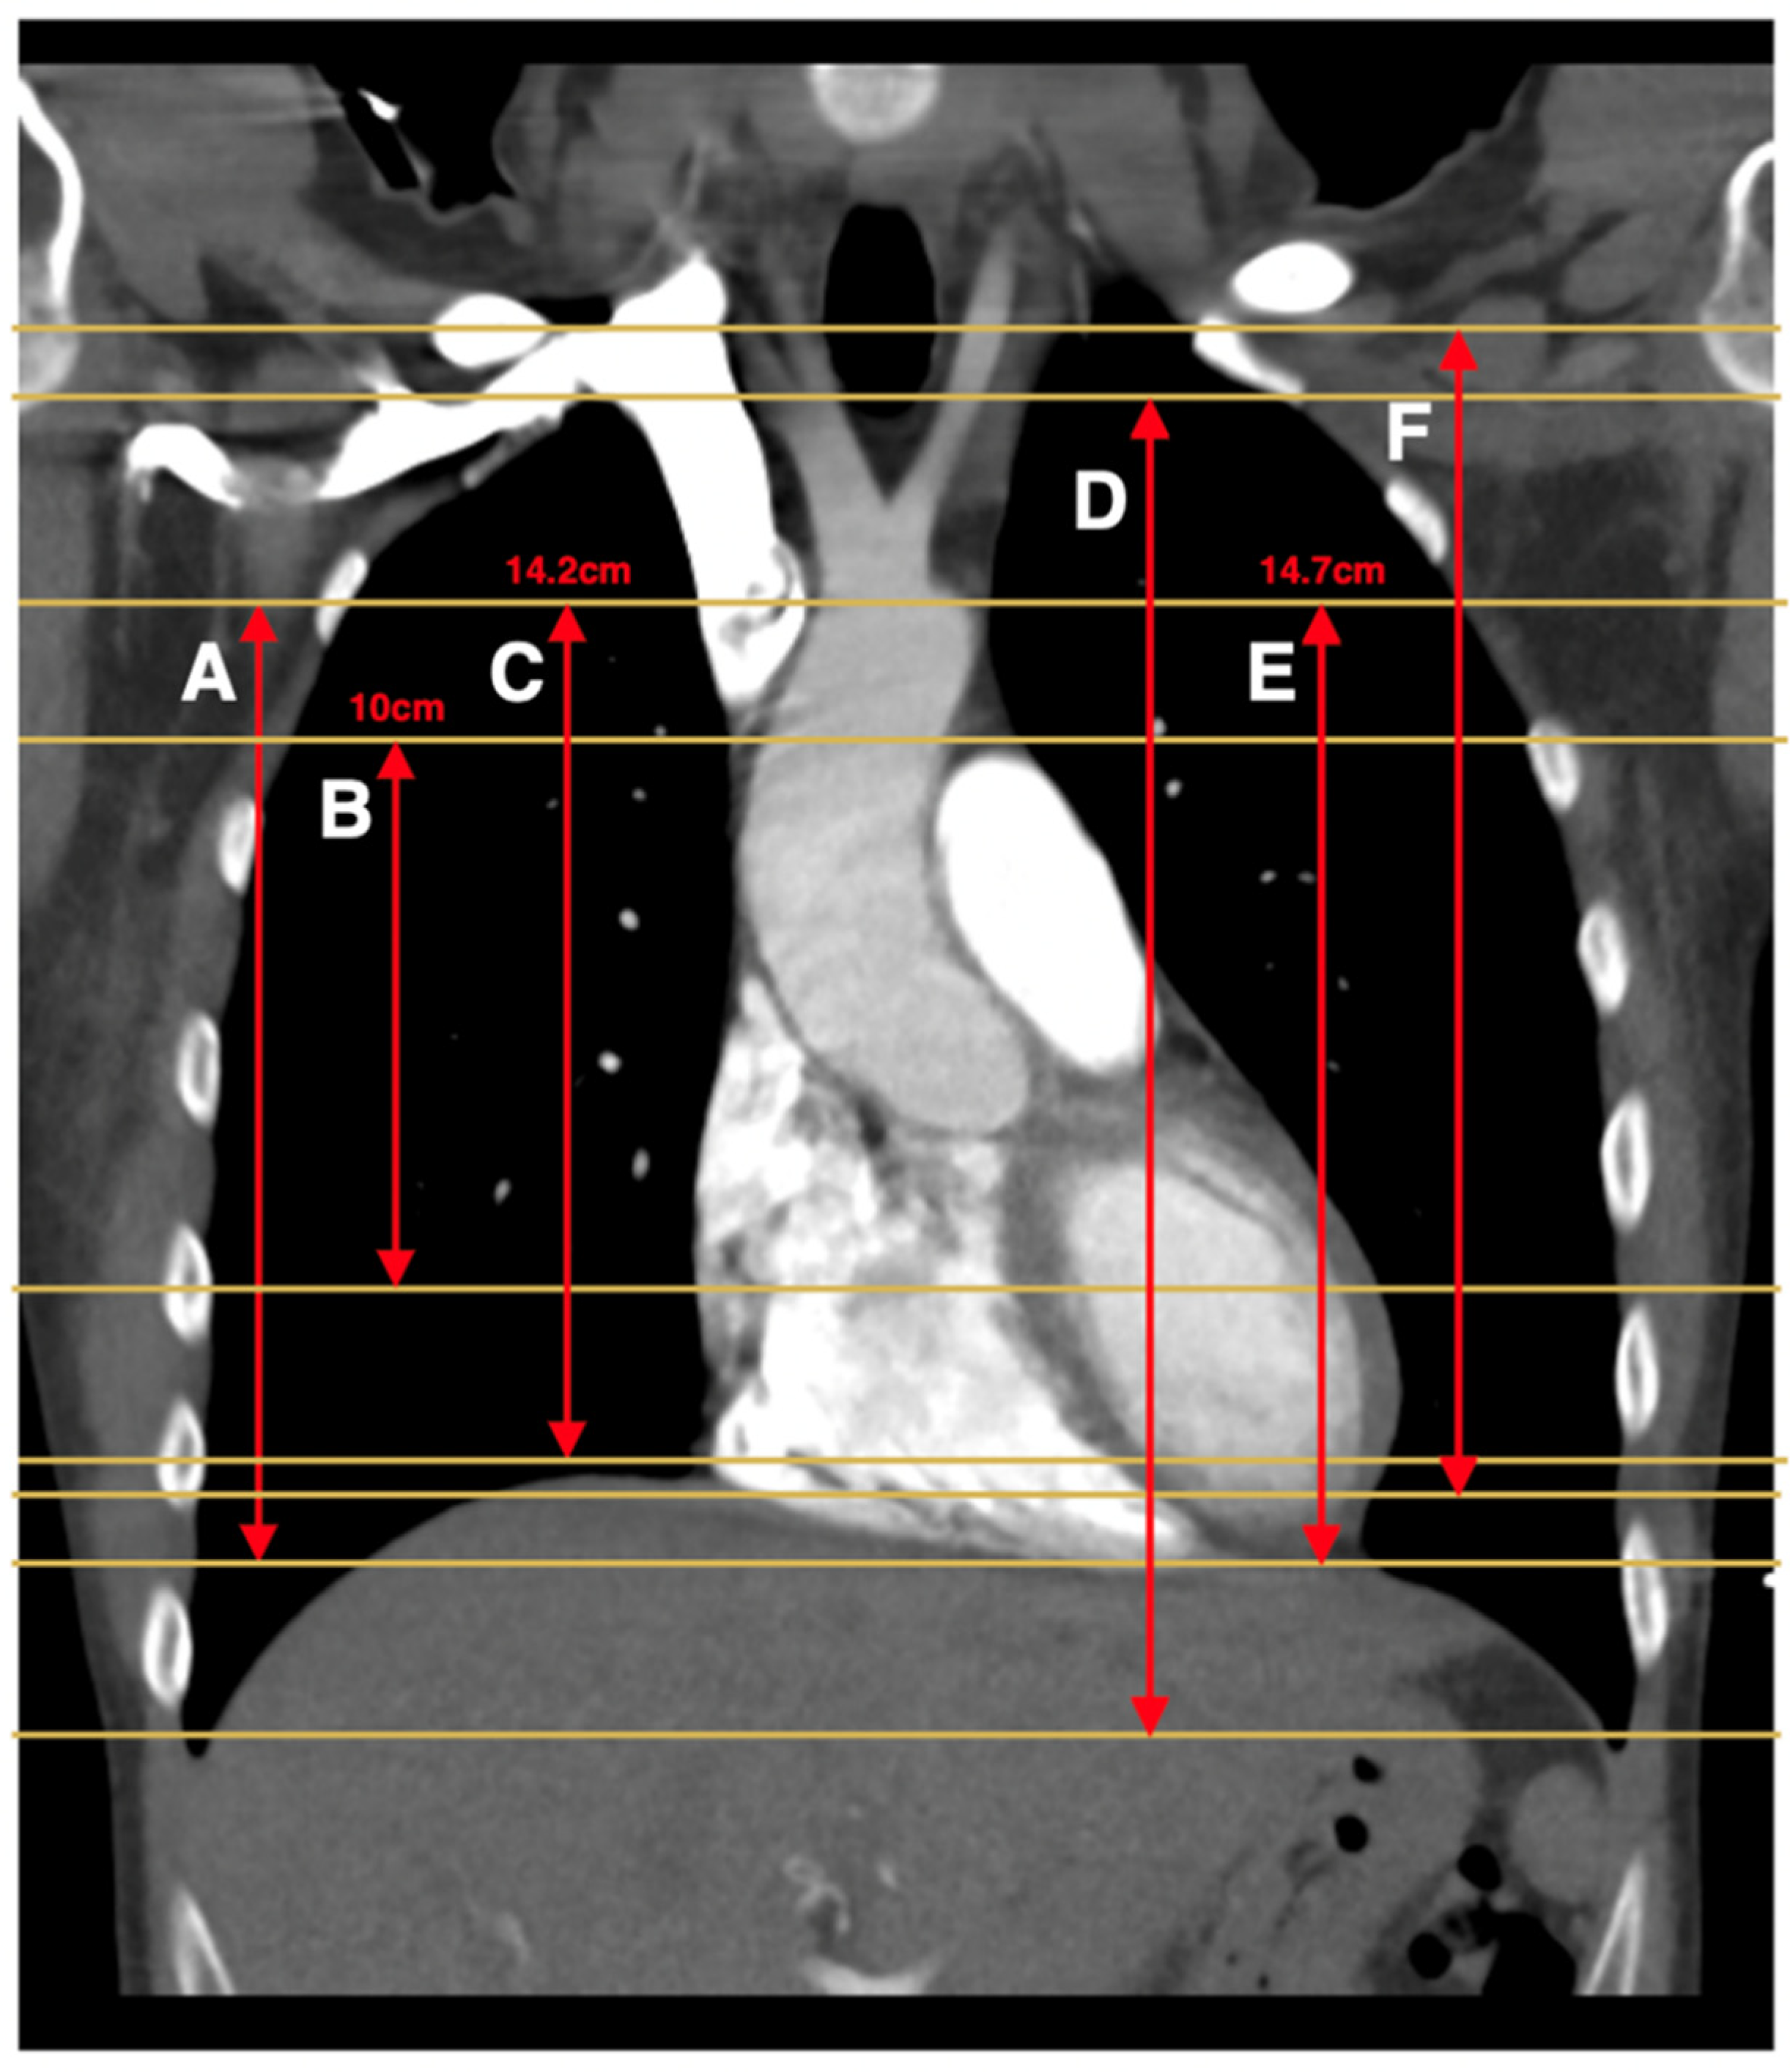

| Atalay et al., 2011 [11] (Clin Rad) | 16-row MDCT | A: 14.2 cm scan length centered 4.1 cm below the carina (capture at least one PE) B: Top of aorta to bottom of the heart | A: Y B: N | A: 11.7 (44%) B: 9.9 (38%) | N/A |

| Atalay et al., 2011 [14] (J Cardiol Comput Tomogr) | 16-row and 64-row MDCT | 14.2 cm scan length centered 4.1 cm below the carina (based on previous study which optimized scan length to capture all PE) | N | 13.8 (49%) | N/A |